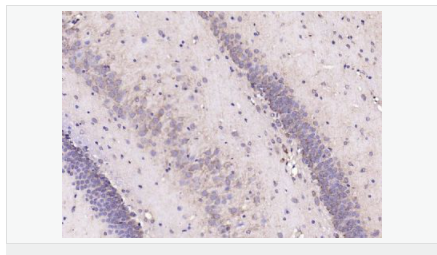

| 產(chǎn)品應(yīng)用 | ELISA=1:5000-10000 IHC-P=1:100-500 IHC-F=1:100-500 IF=1:200-800 (石蠟切片需做抗原修復) not yet tested in other applications. optimal dilutions/concentrations should be determined by the end user. |

| 產(chǎn)品介紹 | This gene encodes a member of the corticotropin-releasing factor family. The encoded preproprotein is proteolytically processed to generate the mature neuropeptide hormone. In response to stress, this hormone is secreted by the paraventricular nucleus (PVN) of the hypothalamus, binds to corticotropin releasing hormone receptors and stimulates the release of adrenocorticotropic hormone from the pituitary gland. Marked reduction in this protein has been observed in association with Alzheimer's disease. Autosomal recessive hypothalamic corticotropin deficiency has multiple and potentially fatal metabolic consequences including hypoglycemia and hepatitis. In addition to production in the hypothalamus, this protein is also synthesized in peripheral tissues, such as T lymphocytes, and is highly expressed in the placenta. In the placenta it is a marker that determines the length of gestation and the timing of parturition and delivery. A rapid increase in circulating levels of the hormone occurs at the onset of parturition, suggesting that, in addition to its metabolic functions, this protein may act as a trigger for parturition. [provided by RefSeq, Nov 2015] Function: This hormone from hypothalamus regulates the release of corticotropin from pituitary gland. Subunit: Interacts (via C-terminus) with CRFR1 (via N-terminal extracellular domain). Subcellular Location: Secreted. Similarity: Belongs to the sauvagine/corticotropin-releasing factor/urotensin I family. SWISS: P06850 Gene ID: 1392 Database links: Entrez Gene: 1392 Human Entrez Gene: 12918 Mouse Omim: 122560 Human SwissProt: P06850 Human SwissProt: Q8CIT0 Mouse Unigene: 75294 Human Unigene: 290689 Mouse Unigene: 10349 Rat Important Note: This product as supplied is intended for research use only, not for use in human, therapeutic or diagnostic applications. CRF陽性神經(jīng)元的胞體廣泛分布于下丘腦的室旁核、背縫核和藍斑核,這些區(qū)域也是去甲腎上腺素(NE)神經(jīng)元與5-羥色胺(5-HT)神經(jīng)元密集的區(qū)域。 CRF既具有神經(jīng)遞質(zhì)的性質(zhì)又具有神經(jīng)激素的性質(zhì)。CRF是聯(lián)系神經(jīng)系統(tǒng)與內(nèi)分泌系統(tǒng)的橋梁,在情感障礙疾患如焦慮和抑郁的發(fā)病中發(fā)揮重要作用. |